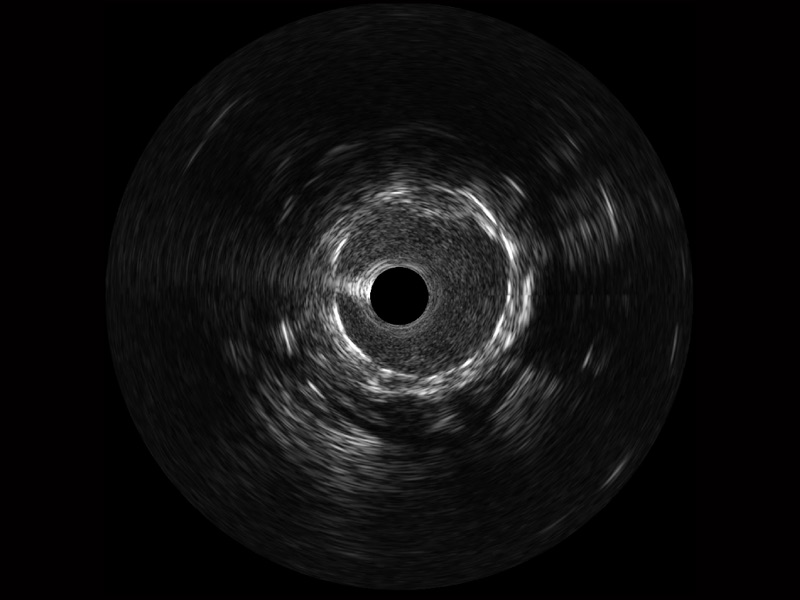

乐玩lewin国际宽频IVUS图像

对比传统IVUS导管成像,乐玩lewin国际宽频IVUS图像的近场支架梁显影更细腻,远场中膜外血管仍清晰可辨,兼顾远中近,兼顾分辨力与穿透深度